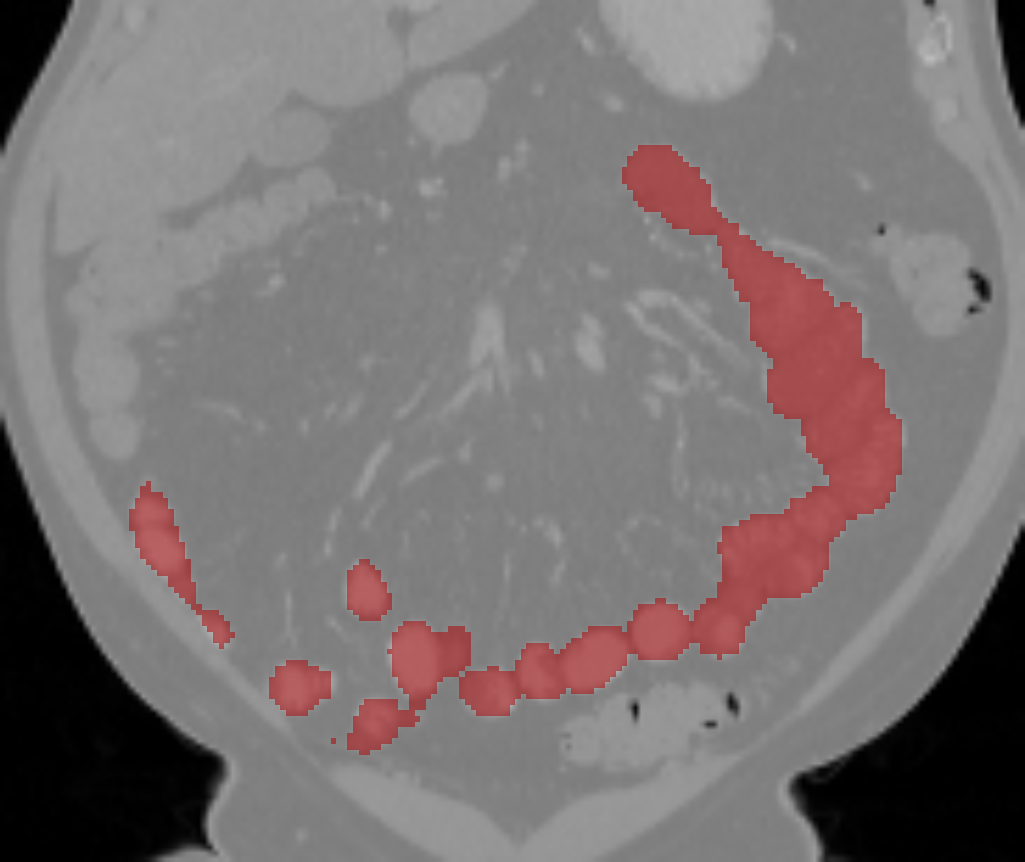

The small bowel has a cylindrical shape but also has many touchings with different parts along its path, which makes it have variable topologies across patients and time. It is inappropriate to apply a constant topological constraint to such organs. Fig. 1 shows an example of the small bowel path covered by the lumpy ground-truth (GT) segmentation.

GT labels were achieved by an experienced radiologist using 3DSlicer111https://www.slicer.org [6] based on the following steps. Firstly, the path of the small bowel is drawn as interpolated curves which connect a series of manually placed points inside the small bowel. Secondly, we grow the curves using a margin of and threshold it again using a Hounsfield unit (HU) range of . Manually drawn air pockets, which have much lower HU values, are also added during the second step. Produced errors are manually fixed in the final step. We note that this annotation procedure took one or two full days for each volume. Finally, the dataset includes the two types of labels, which are the path and segmentation of the small bowel as shown in Fig. 1.

Fig. 3 shows example segmentation results. The proposed method eliminates false positives on the large bowel by the help of the applied topological constraint. Fig. 4 further clarifies the effectiveness of the proposed method by presenting 3D rendered segmentations. The proposed method produces a more topologically correct segmentation of the small bowel with fewer false positives. Fig. 5 presents example barcode diagrams, which again show the reduced numbers of connected components and holes within the segmentation result of the proposed method.